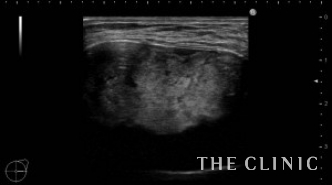

この方は2年前に他院にてバッグ抜去+脂肪注入(片側400㏄)を受けられています。その際、被膜の中に脂肪が入ってしまい血流が途絶えたために脂肪壊死となりしこりになってしまったようです。一番大きい物で6㎝の充実性のしこりがありました。(左の画像)その他にもオイル状の小さいしこりがいくつかあり、皮下にあるものは針で刺してオイルを吸引除去しました。(右の画像)

6㎝のしこりの被膜は肥厚し、内部は充実性のしこり(脂肪壊死)とオイルの両方を認めます。肥厚した被膜を破りチューメセント(麻酔)を注入して、脂肪壊死を崩すためベイザーリポを使用します。